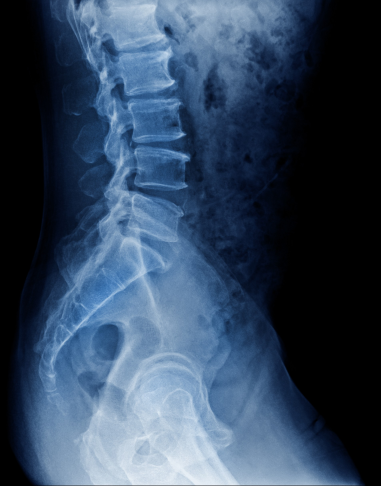

Röntgen, MR & Ultraljud

Kan vara en del av vägen till din diagnos.

Som en del av din utredning på Kroppia gör vi en noggrann klinisk bedömning av om bilddiagnostik är nödvändig för att fastställa rätt diagnos eller säkerställa att behandling kan ske tryggt.

Vi börjar alltid med en grundlig klinisk funktionsanalys. Bilddiagnostik används som ett precisionsverktyg när vi behöver bekräfta fynd eller utesluta bakomliggande orsaker som inte syns vid en manuell undersökning.

Vi går igenom dina röntgen- eller MR-svar tillsammans. Det viktigaste är hur bilderna korrelerar med din biomekaniska status, så att vi kan utforma en träffsäker behandlingsplan.

Tolkning & Åtgärd